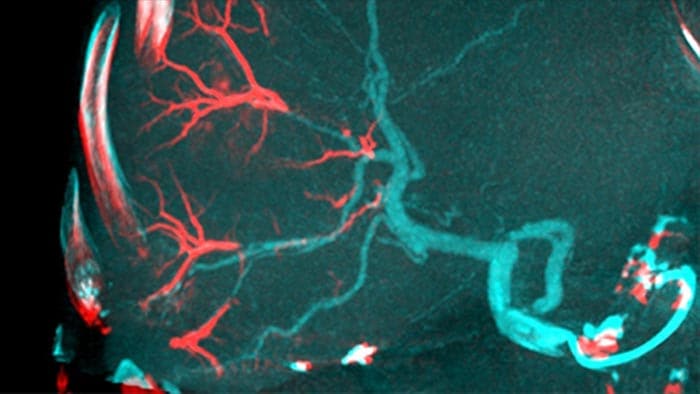

La solución de Detección Automática de vasos Alimentadores puede mejorar significativamente la detección de arterias dependientes. EmboGuide le ayuda a maximizar la eficacia de sus procedimientos TACE, ya que potencialmente mejora su sensibilidad, reduce los falsos positivos y maximiza el acuerdo entre lectores1. EmboGuide también proporciona una guía 3D en vivo eficiente y basada en el flujo de trabajo con detección automática de vasos alimentadores1.

La adopción de técnicas de quimio/radioembolización como TACE y SIRT impulsa la necesidad de estandarización y eficiencia. Caso tras caso, debe localizar de manera confiable y consistente los tumores, identificar todos los vasos dependientes y planificar /ejecutar el enfoque intervencionista apropiado. Nuestra solución de Detección Automática de vasos Alimentadores puede mejorar significativamente la detección de arterias dependientes en comparación con el uso de CT de haz cónico solo. EmboGuide le ayuda a maximizar la eficacia de sus procedimientos TACE, ya que potencialmente mejora su sensibilidad, reduce los falsos positivos y maximiza el acuerdo entre lectores.1

La capacidad de detectar y de distinguir nódulos hepáticos e identificar los recipientes minúsculos del vaso alimentador es crítica para determinar terapia apropiada. Navegar a la región de interés llegando a todos los vasos alimentadores, sin dejar de ser selectivo con la lesión, aumenta la oportunidad de éxito. La confirmación del criterio de valoración del tratamiento y el éxito del mismo mientras el paciente todavía está sobre la mesa aumenta la confianza en los resultados clínicos.

CBCT Dual permite la adquisición 3D de una fase arterial para visualizar estructuras vasculares y una post-arterial (fase retardada) para visualizar la acumulación de medio de contraste, en un solo paso automático5.

Dual View permite la visualización simultánea de dos conjuntos de datos CBCT. Tanto la fase arterial como la retardada pueden mostrarse una al lado de la otra o en una sola vista de superposición fusionada.